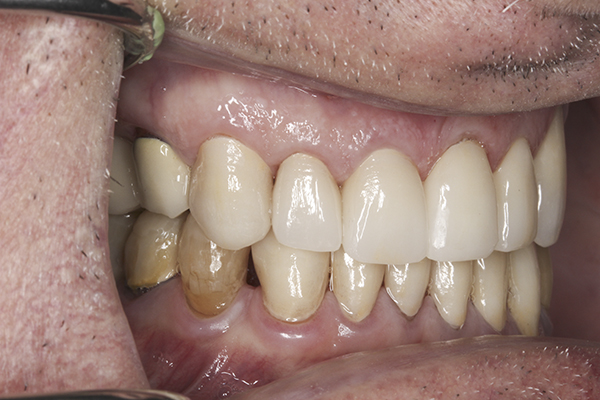

(35.) Postoperative right lateral, closed view.

Figure 35

(36.) Postoperative anterior, closed view. Note the position of the upper and lower canines to provide canine guidance.

Figure 36